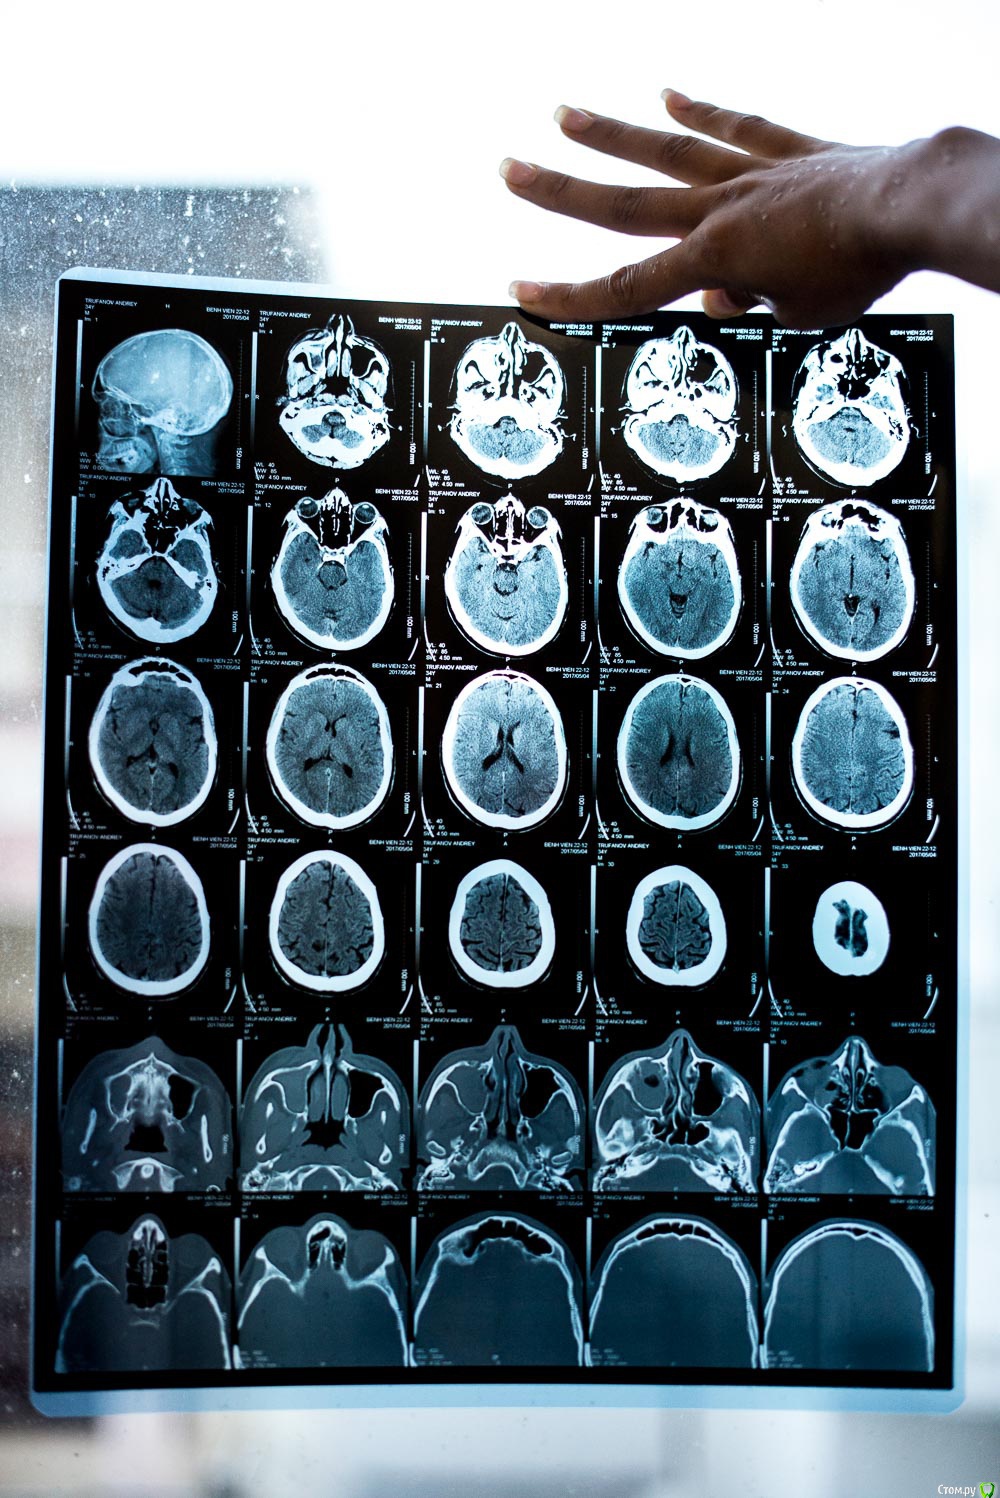

andrei_trufanov Опубликовано 4 мая, 2017 Поделиться Опубликовано 4 мая, 2017 Добрый день ! Требуется Ваш помощь, обратиться больше некуда , ситуация такая нахожусь сейчас длительное время во Вьетнаме, 1мая получил травму лица , сегодня был у лора ,сделал КТ, врач сказал что перелом лицевой кости и воспаление и что операцию делать не нужно или он не могут, не совсем понял , назначил лекарства и просил прийти через 10 дней. Подскажите на сколько серьезна ситуация нужна ли операция если да , то как срочно и правильны ли назначены лекарства ? Augmentin BD 1000mgAlpha chymotrypsin (AL-KIISIN)Methyl prednisolon 16mg(Medrol)Mequitazine 5mg(ITAMETAZIN)Acetylcystein 200mg(ACEMUC 200)Otrivin 0.1% Nosal Spray 10mlBudesonide 64mcg (BENITA) Ссылка на комментарий

St. Опубликовано 4 мая, 2017 Поделиться Опубликовано 4 мая, 2017 Перелом есть. Воспаление в гайморовой пазухе по снимку тоже есть. Так что с диагостикой все верно. 2 Ссылка на комментарий

ПалСаныч Опубликовано 4 мая, 2017 Поделиться Опубликовано 4 мая, 2017 Лично мое мнение: перелом есть. Смещение небольшое. В пазухе кровь. Если рот открывается в полном объеме, нет двоения в глазах и под глазом пальцем не ощущается костной ступеньки, то и жить спокойно дальше. Из назначенного оставил бы аугметин и спрей в нос. 6 Ссылка на комментарий

Irouil Опубликовано 4 мая, 2017 Поделиться Опубликовано 4 мая, 2017 Рот открывается? Если да, то спим на другой стороне и все. Больше ничего делать на данный момент не требуется, воспаления нет, в пазухе кровяка, смещение выглядит минимальным. Период бережливого отношения к лицу - месяц, потом можете еще раз ломать)) Аугментин допивайте, я бы еще антигистаминные назначил - лоратадин/дезлоратадин по 1-2 в сутки или цетиризин/супрастин на ночь по таблетке, ну и спрей, да. Вообще я почти во всем тут с Павлом Александровичем согласен. Ссылка на комментарий